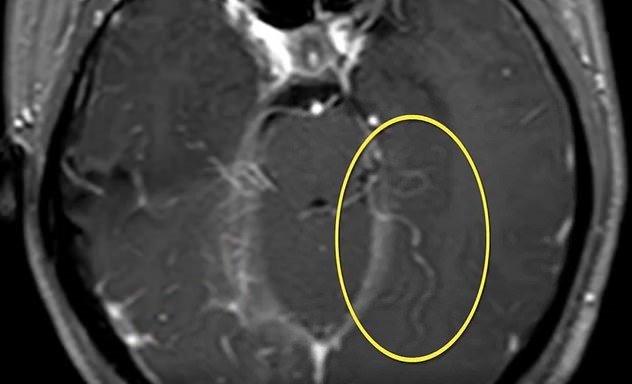

After Xiao Yi tested positive for being infected with parasites, doctors performed brain surgery on her.

“During the operation, we found a creeping, long bug that was over 10 centimetres. It was white and live, like a noodle,” Dr. Dai Wei of the Gulou Hospital of Nanjing University said.

“It was still moving around when we took it out completely.”

According to reports, the worm was measured to be six inches (15 centimeters) long.